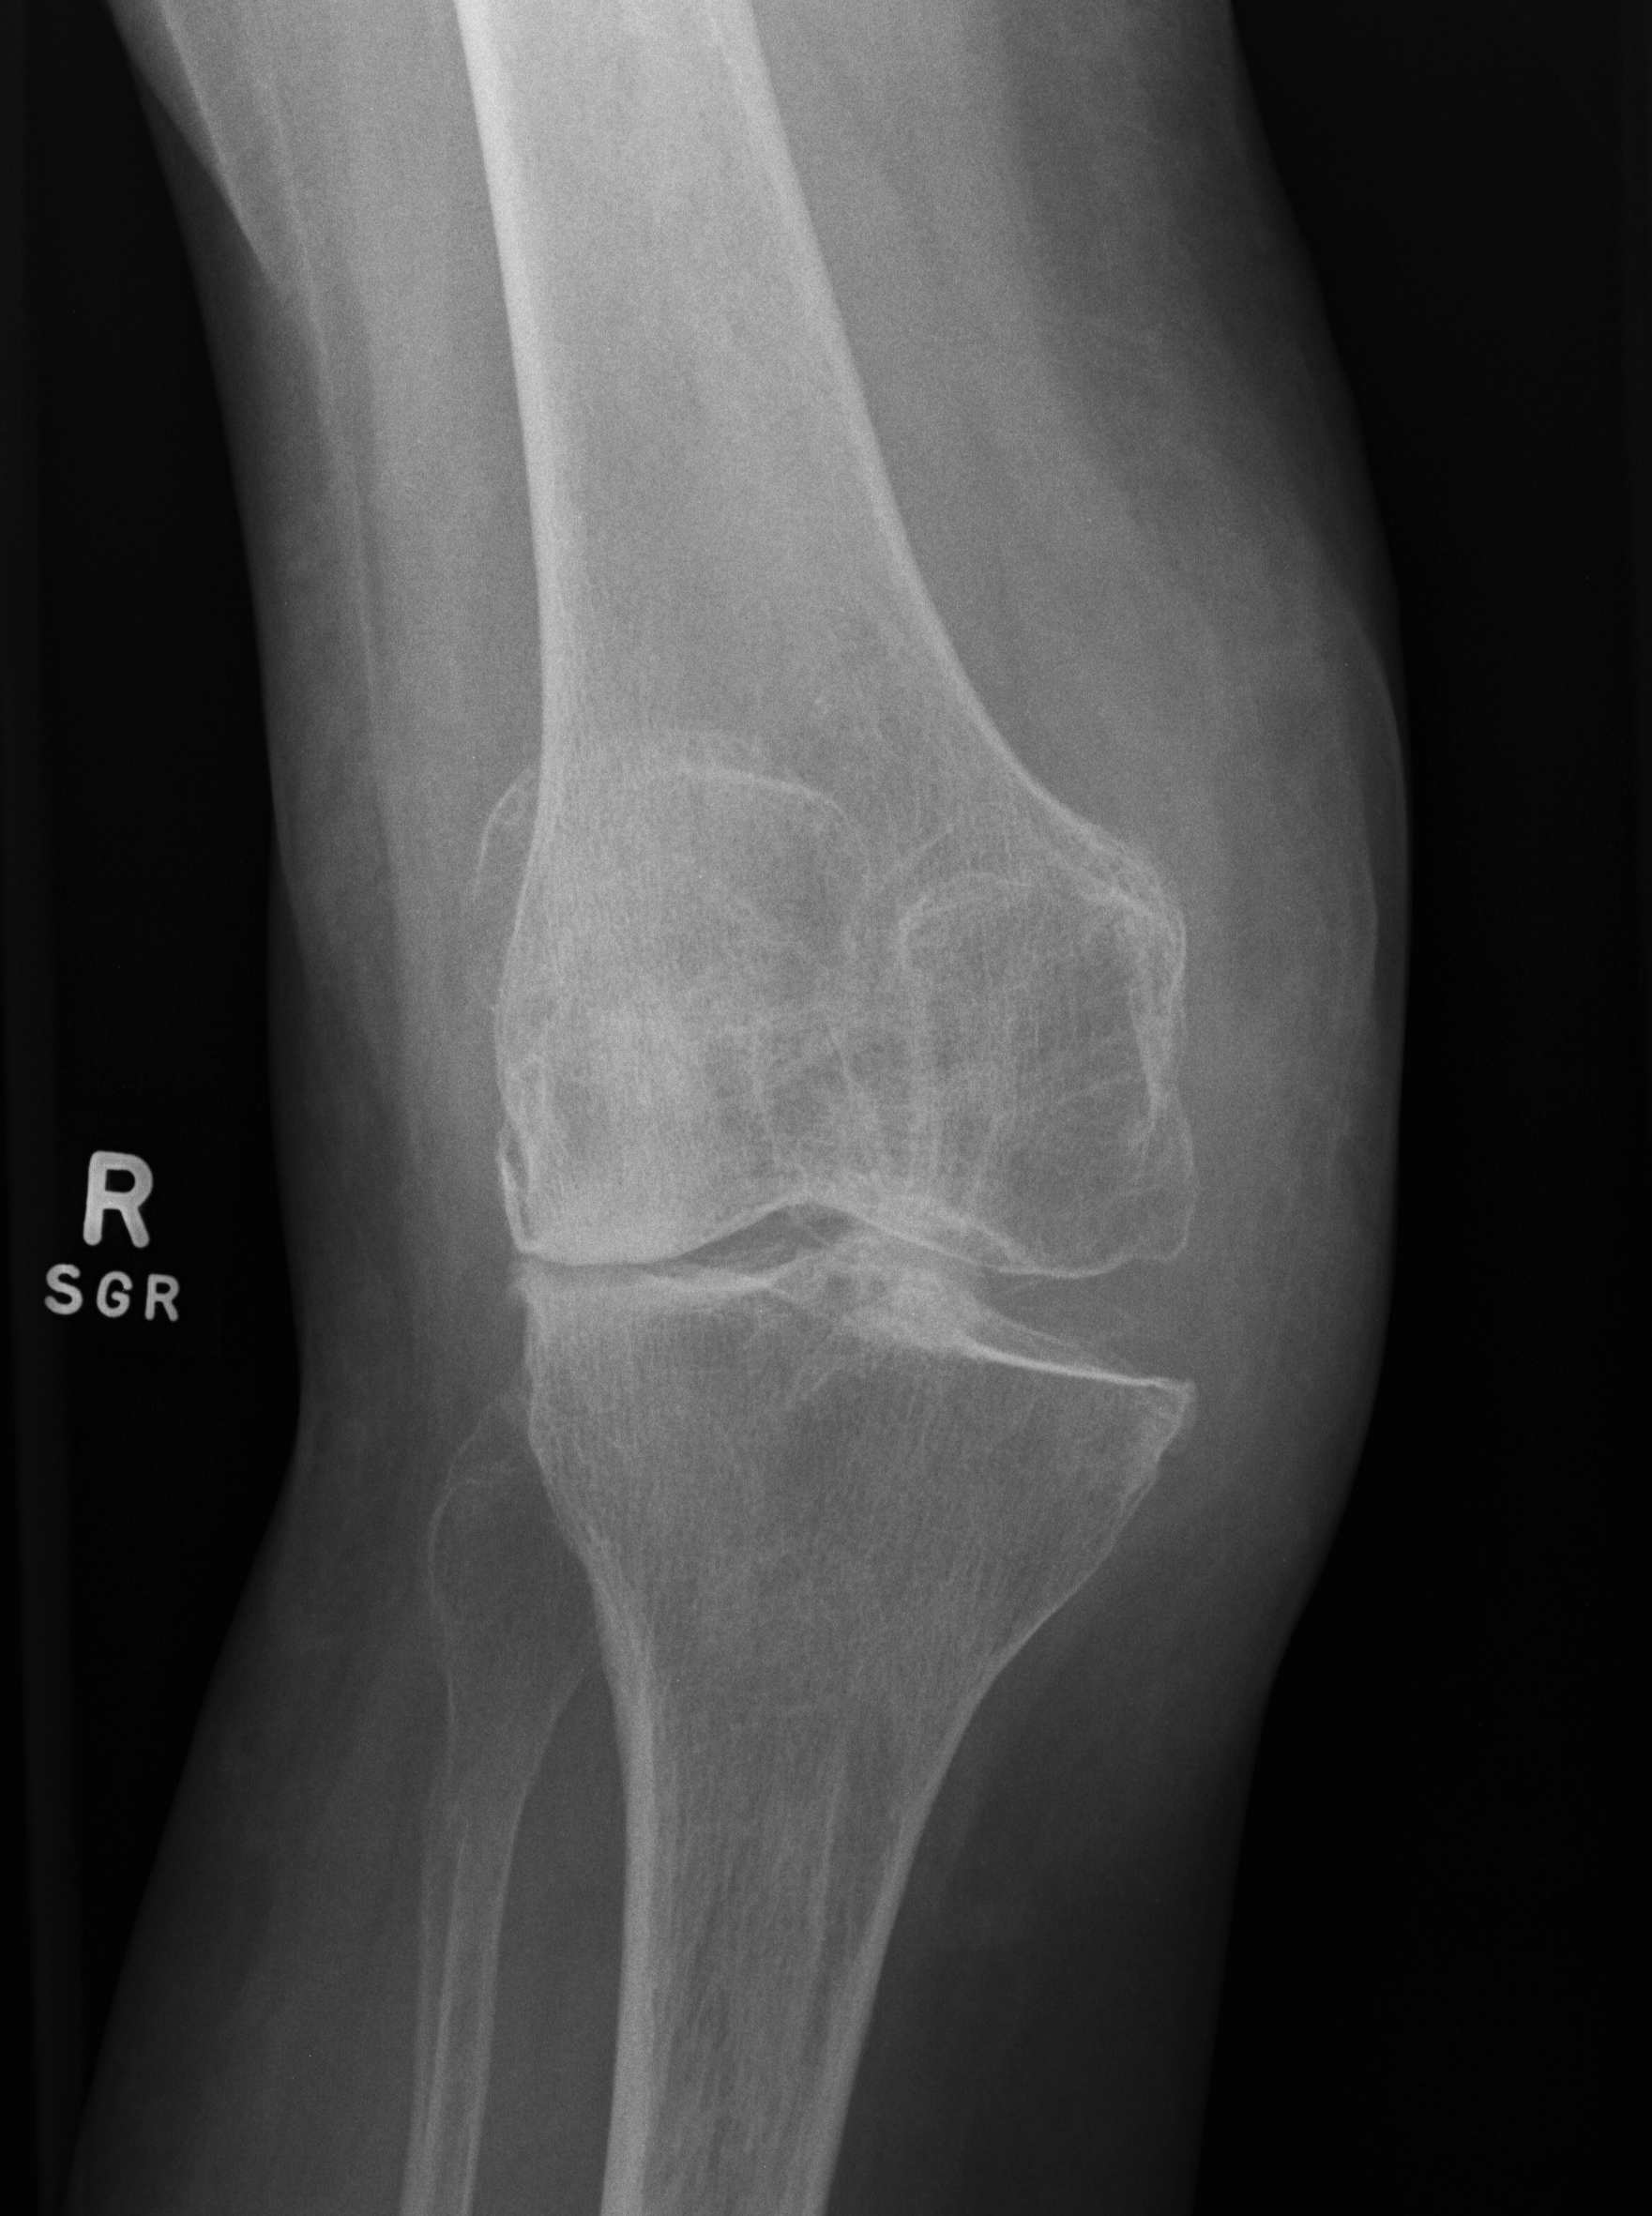

TKR Moderate Valgus OAValgus Malalignment

A valgus knee has a tibiofemoral angle of > 10o

Pathology

Bony abnormalities

A.  LFC hypoplasia

- beware posterior condyle referencing